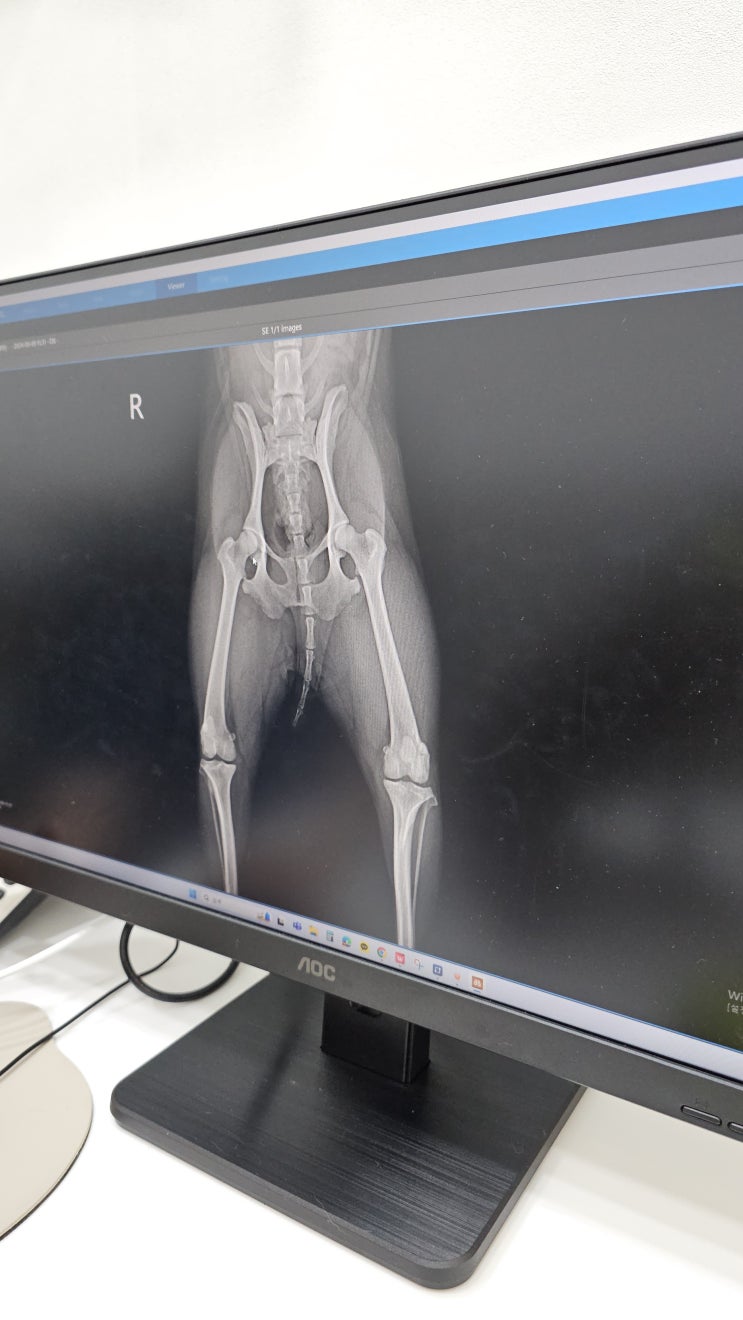

부평 동물병원 24시부평종합동물의료센터 강아지 슬개골탈구 검사

안녕하세요. 푸들 순희맘 이에요 :) 우리집 막내 순희는 집에서 인형 던져주면 받아오는 놀이를 최고로 좋...